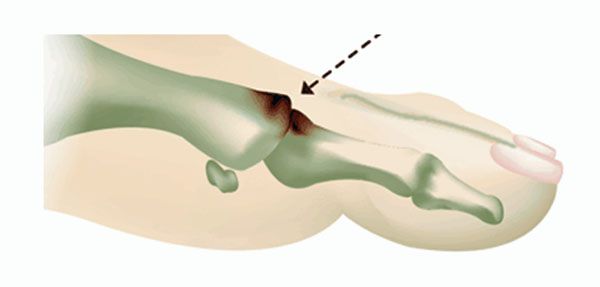

Eine Arthrose des Großzehengrundgelenkes (Hallux rigidus) kann sehr schmerzhaft sein und die normale Fortbewegung stark beeinträchtigen. Die Therapie ist abhängig vom Stadium der Erkrankung. Bei milden Arthrosen mit nur endgradigen Bewegungseinschränkungen kann trotz des Knorpelverfalls häufig gelenkerhaltend therapiert werden. Die Methode wird als Cheilektomie bezeichnet. Es werden überstehende Knochenvorsprünge (Osteophyten) abgetragen und die Gelenkflächen verjüngt. Das Bewegungsausmaß wird verbessert und die Schmerzen deutlich reduziert. Liegt neben der Arthrose auch eine Fehlstellung (Hallux valgus) vor kann der Eingriff mit einer Korrektur der Zehenstellung kombiniert werden.

Abb.5: Großzehengrundgelenk mit Arthrose und Knochenanbauten. Die mit dem Pfeil markierten Anbauten werden bei der Cheilektomie abgetragen.